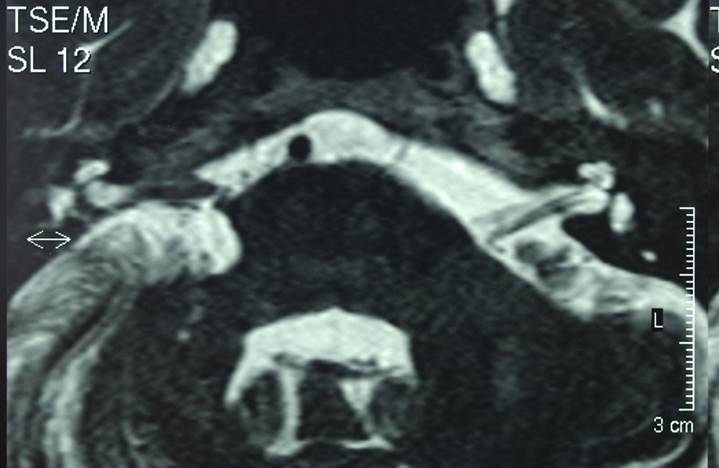

Figure 6

T2 weighted spin echo MRI showing large right acoustic neuroma with significant brainstem compression